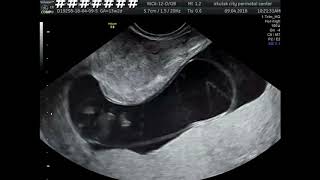

Случай правосторонней диафрагмальной грыжи

Диафрагмальная грыжа

Диафрагмальная грыжа – аномалия развития, характеризующийся наличием врожденного дефект диафрагмы, через который, во внутриутробном ...